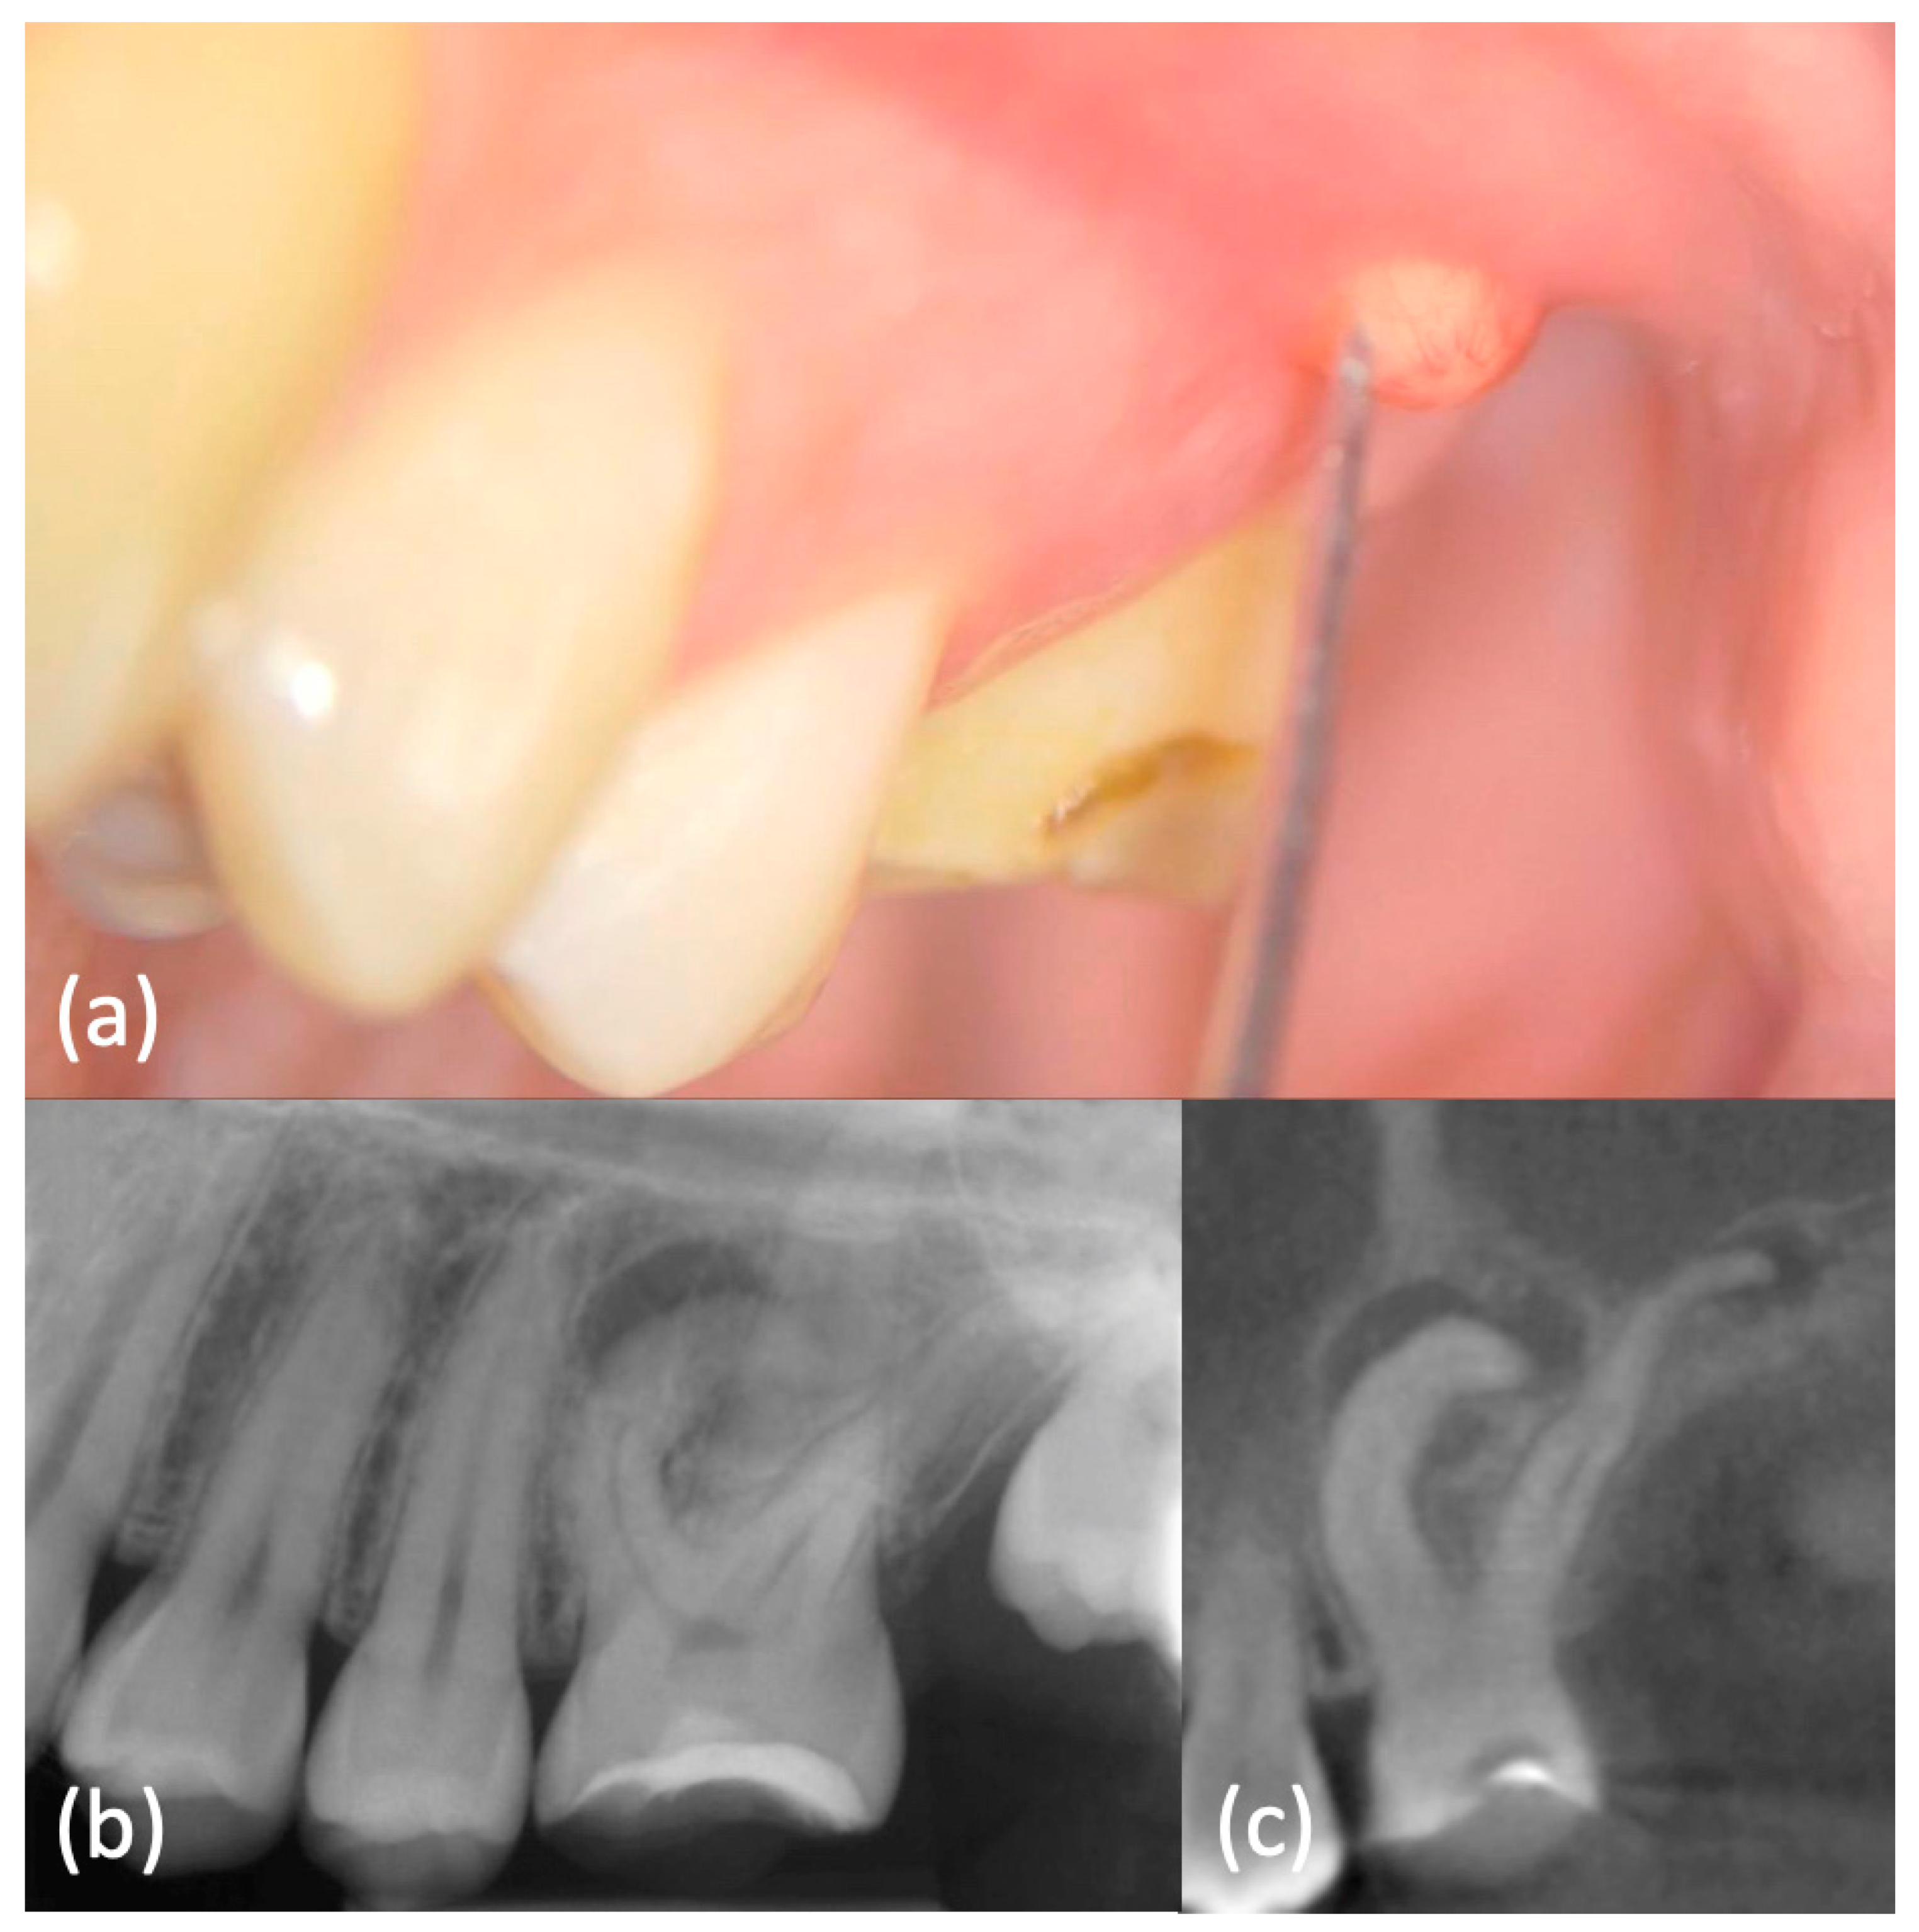

History and physical examination: A 16-year-old otherwise healthy female was seen in emergency because of pain in her right maxillary region. An extraoral examination did not reveal swelling or other abnormalities. An intraoral examination showed immediately the presence of a lump on the buccal aspect of the tooth 26, which appeared not to be completely erupted and with a typical aspect of dilacerated root morphology on 2D radiographic imaging. A carious lesion was present on the same tooth and element 27 was not erupted (Figure 6a–Movie 6).

Figure 6.

(a) Intraoral examination showed a lump on buccal side of element 2.6, which appeared not to be completely erupted and with a carious lesion. Element 2.7 was clinically absent. (b) Periapical X-ray showed dilacerated roots of element 2.6, with a periapical lesion on the mesial-buccal one. Element 2.7 was not erupted, but present. (c) CBCT confirmed these findings and highlighted a periapical lesion also on the other roots.

Tooth 26 did not respond to sensitivity testing and it was tender to percussion and palpation, whereas the other elements responded normally. The electric pulp vitality test confirmed the pulpal necrosis of 26. Periodontal pocket values were between 1 mm up to 3 mm, without bleeding on probing.

Imaging examination and diagnosis: A pre-operative periapical image (Figure 6b) was carried out by long-cone paralleling technique (CS 2200, Carestream Dental, Rochester, NY, USA). It confirmed the presence of dilacerated mesio- and disto-buccal roots and the diagnosis of chronic periapical periodontitis. The tooth 27 was not erupted because of aberrant root morphology of the mesial element.

This radiography had an important role in the preliminary assessment of the irregular morphology of the root canal system, but it provided only a 2D-representation of the complex anatomy. Therefore, a small-FOV CBCT (Figure 6c–Movie 7) was indicated based on the current ESE guidelines. It provided a 3D image of the dilacerated tooth and its surrounding tissues and helped to determine the exact position and angulation of the dilaceration abnormality, which was found to also affect the palatal root. Apical radiolucencies were detected within the woven bone surrounding the apices of all roots. These diagnostic findings could be obtained only with CBCT imaging. An orthograde primary root canal treatment was recommended to the patient.